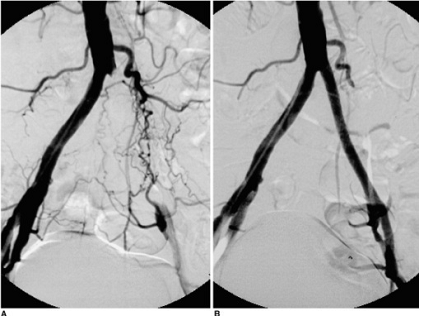

пациенту, составившим основную группу выполнены эндоваскулярные операции:

стентирование подвздошных (см. Рисунок 2) и бедренных артерий, баллонная

ангиопластика и стентирование бедренно-подколенного сегмента выполнены.

Рисунок 2. Стентирование подвздошных артерий.